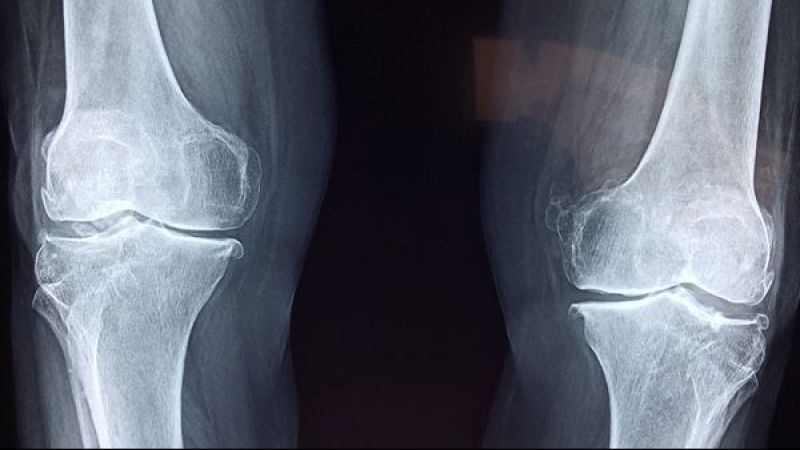

Genel olarak dizlerde, ellerde, omurgada ve kalçalarda meydana gelen kireçlenme tedavi edilmesi gereken önemli bir sağlık sorunudur. Kişilerle en çok görülen kronik eklem sorunlarının başında gelen kireçlenmenin bütün eklemleri etkiliyor olması sağlık adına son derece riskli. Kireçlenme genel olarak yaşlılarda meydana gelse de her yaştan birini de etkisi altına alabilir. Kireçlenmenin en önemli özelliklerinden biri eklemlerde kalsiyum tuzunun birikmesidir. Ağırlık yüklenen eklenme çok sık görülen kireçlenmenin çeşitli sebepleri bulunur.

Normal yaşamda eklemler sürekli olarak aşınmaya maruz kaldığı ve kemiklerde vücut bu durumu onaramadığından dolayı kireçlenme yaşanır. Sorun genel olarak orta ve ileriki yaştaki kişilerde meydana gelir. Yaşın ilerlemesi ile eklemler ve kemiklerdeki kıkırdak yapısı değişir. Bundan dolayı kemiklerin dayanıklılığı azalır. Başka bir faktör ise genetik yapıdır. Vücudun kıkırdak yapısını meydana getiren kolajen üretimine görülen kusurlar genetik yapıya bağlı olarak kireçlenme rahatsızlığında rol sahibi olur. Bunlar haricinde obezite, hareketsiz bir yaşam sürmek ve yaralanmak da eklemlerde kireçlenmeye sebep olan etkenler arasında yer almaktadır.